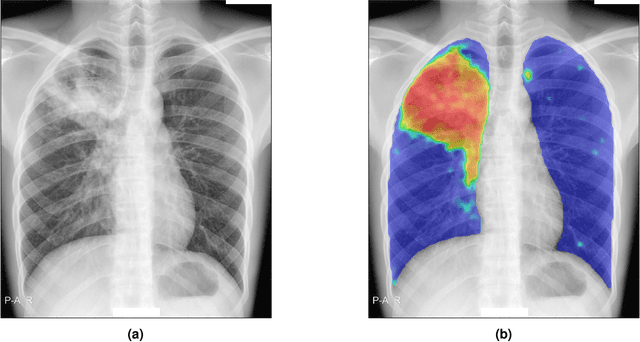

There is a growing interest in the automated analysis of chest X-Ray (CXR) as a sensitive and inexpensive means of screening susceptible populations for pulmonary tuberculosis. In this work we evaluate the latest version of CAD4TB, a software platform designed for this purpose. Version 6 of CAD4TB was released in 2018 and is here tested on an independent dataset of 5565 CXR images with GeneXpert (Xpert) sputum test results available (854 Xpert positive subjects). A subset of 500 subjects (50% Xpert positive) was reviewed and annotated by 5 expert observers independently to obtain a radiological reference standard. The latest version of CAD4TB is found to outperform all previous versions in terms of area under receiver operating curve (ROC) with respect to both Xpert and radiological reference standards. Improvements with respect to Xpert are most apparent at high sensitivity levels with a specificity of 76% obtained at 90% sensitivity. When compared with the radiological reference standard, CAD4TB v6 also outperformed previous versions by a considerable margin and achieved 98% specificity at 90% sensitivity. No substantial difference was found between the performance of CAD4TB v6 and any of the various expert observers against the Xpert reference standard. A cost and efficiency analysis on this dataset demonstrates that in a standard clinical situation, operating at 90% sensitivity, users of CAD4TB v6 can process 132 subjects per day at an average cost per screen of \$5.95 per subject, while users of version 3 process only 85 subjects per day at a cost of \$8.41 per subject. At all tested operating points version 6 is shown to be more efficient and cost effective than any other version.